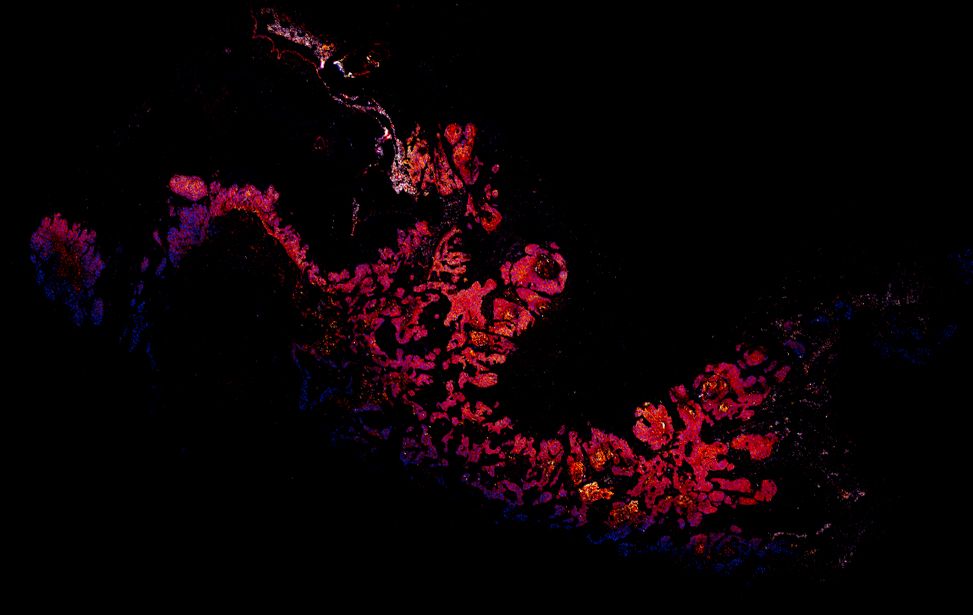

Denis obtained his PhD from the University of Zurich and ETH Zurich in the laboratory of Prof. Bernd Bodenmiller where he worked on Imaging Mass Cytometry and corresponding analysis tools focusing on highly multiplexed image analysis. Prior to this, he received his diploma (Dipl. Biol. (t.o)) at the University of Stuttgart and Harvard Medical School working with Prof. Peter Sorger and Prof. Alfred Goldberg.